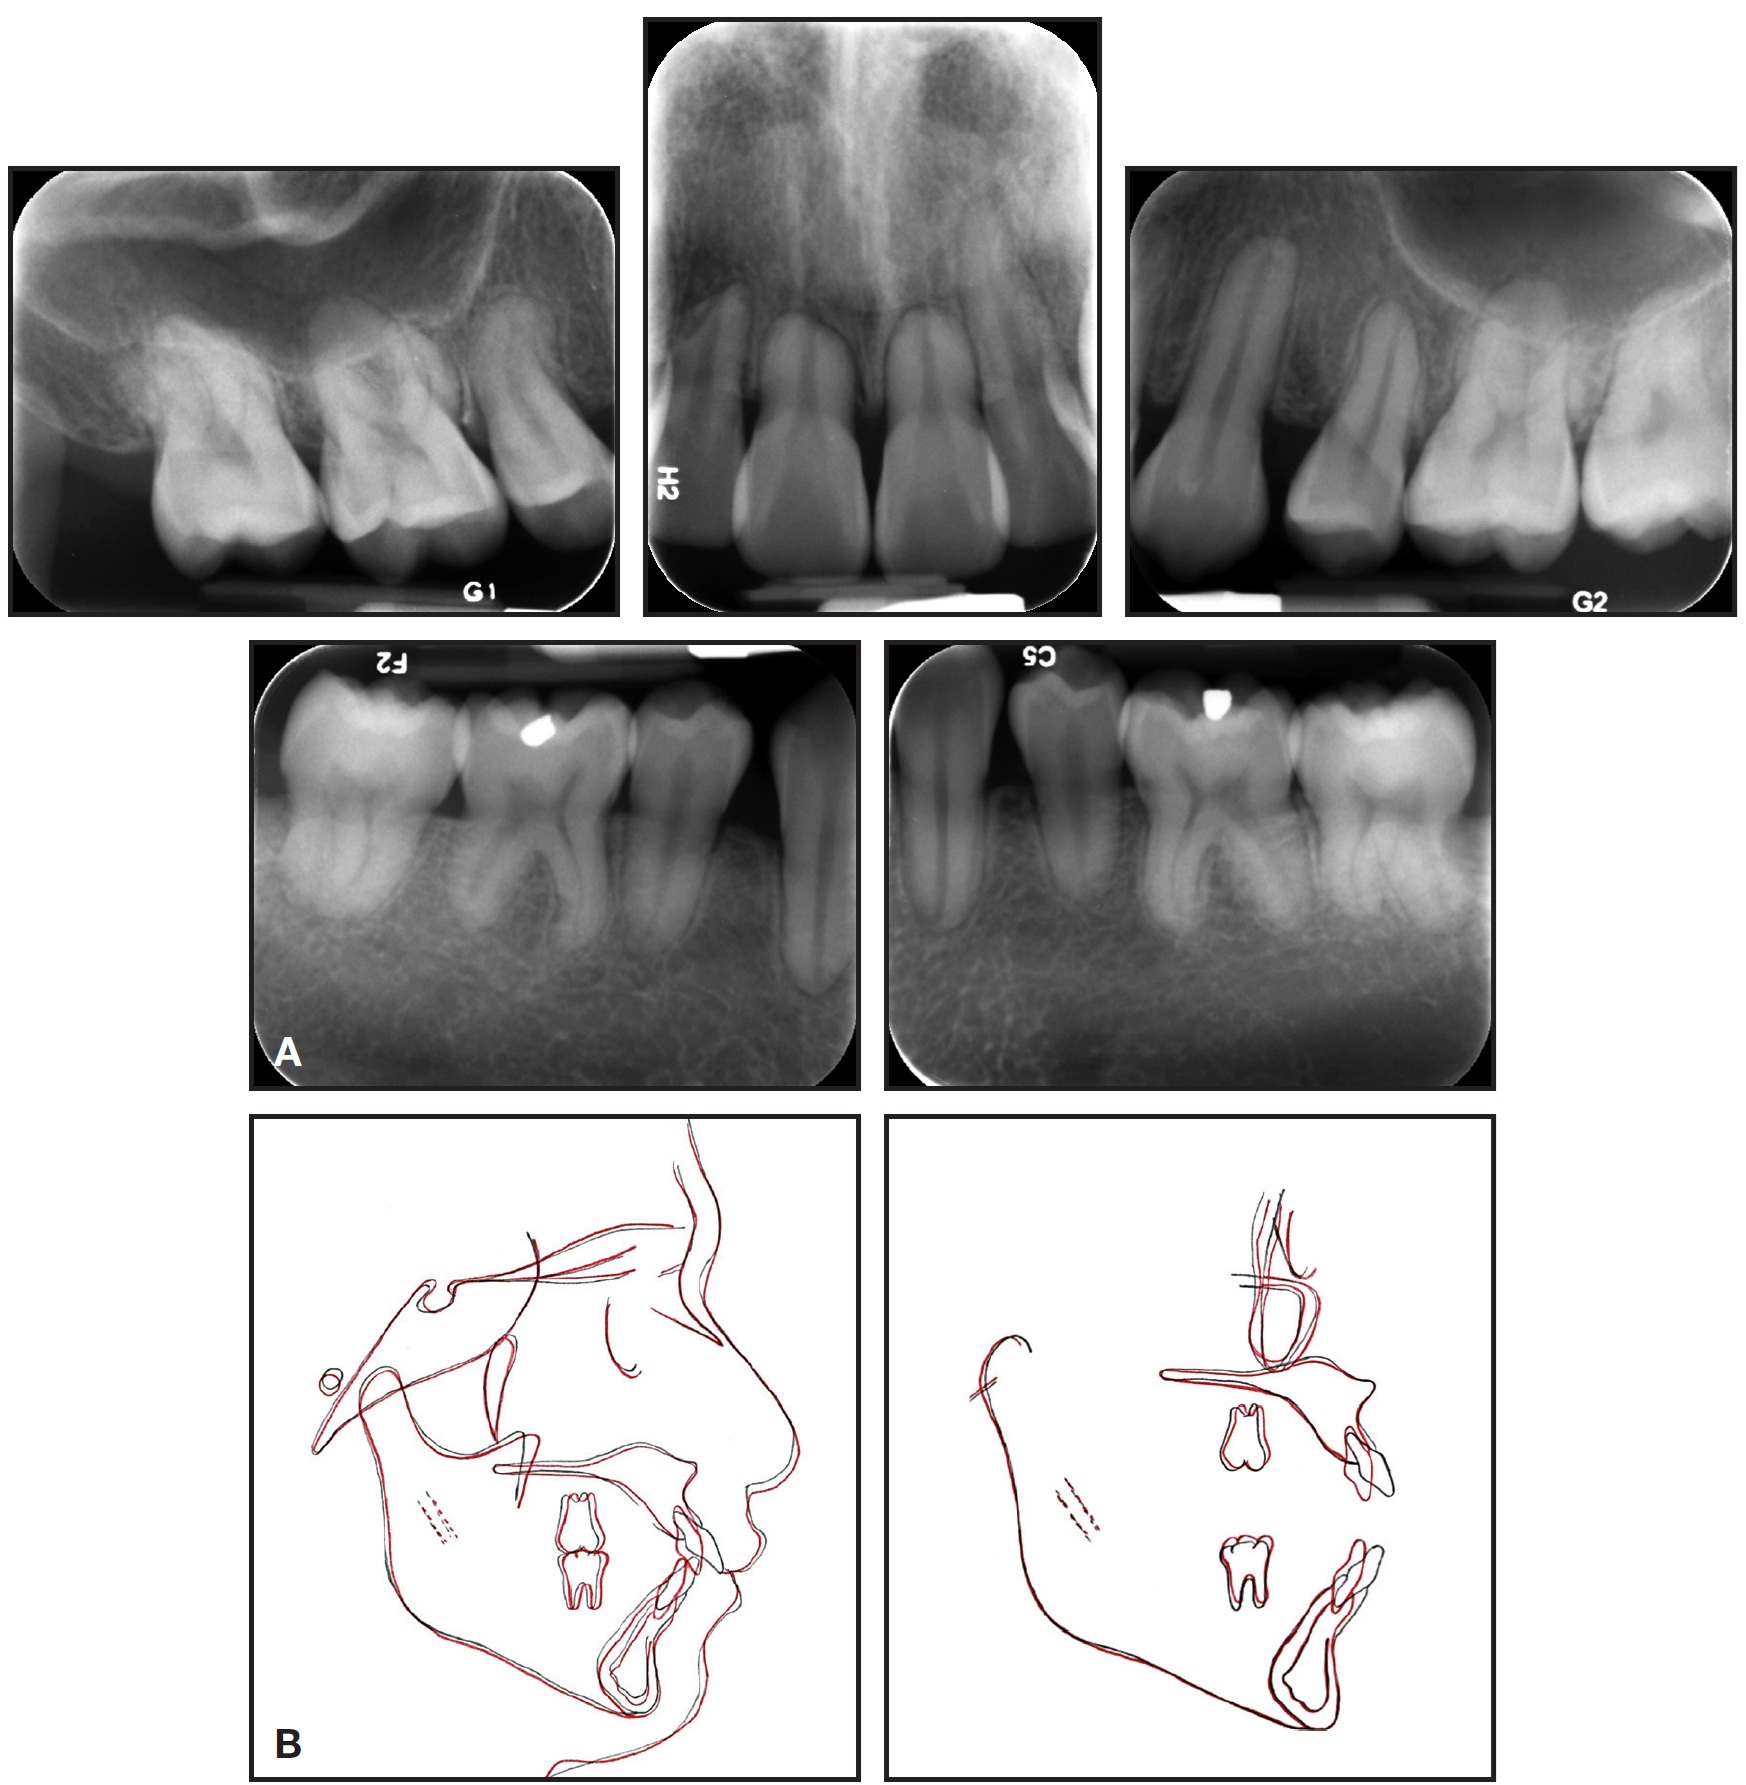

Cephalometric analysis indicated a Class II skeletal base and a convex profile due to a prognathic maxilla. The upper incisors were proclined, and both lips were protruded in relation to the E-line (Table 1). The panoramic radiograph revealed generalized short roots, impacted lower third molars, and a missing upper right third molar.

The root/crown ratios for the first molars, premolars, canines, and upper incisors were calculated as proposed by Lind.1 The most affected teeth were the upper right and left central incisors, with root/crown ratios of .85 and .90, respectively (Table 2).

The patient and his mother reported that no other family members had been diagnosed with short roots. Two brothers of the patient had been previously treated in our clinic and did not present with generalized SRA, but one displayed mild shortening of the premolars—a condition that worsened slightly during orthodontic treatment (Fig. 2).

Fig. 2 Patient’s brother before (A) and after (B) orthodontic treatment.

Favorable dental and soft-tissue relationships were achieved, and the patient was pleased with the results. Both arches were well aligned; a Class I buccal occlusion was maintained on the right side, but the avoidance of intermaxillary elastics resulted in a slight loss of anchorage on the left side during final incisor retraction. The overjet was substantially reduced (from 7mm to 2mm), improving the lip position, smile esthetics, and profile. Cephalometric superimpositions indicated a slight decrease in the ANB angle and convexity (Fig. 7B).

Fig. 7 (cont.) B. Superimposition of pre- and post-treatment cephalometric tracings.

The upper incisors were substantially retracted, and the lower incisor inclination was reduced. There was improvement in the lip projection, especially the lower, in relation to the E-line (Table 1). The length of the roots—including those of the canines, which underwent active retraction for about 20 months—was basically unchanged from the initial radiograph (Table 2). Because the lower third molars showed significant mesial angulation, they were recommended for removal, along with the unopposed upper left third molar.